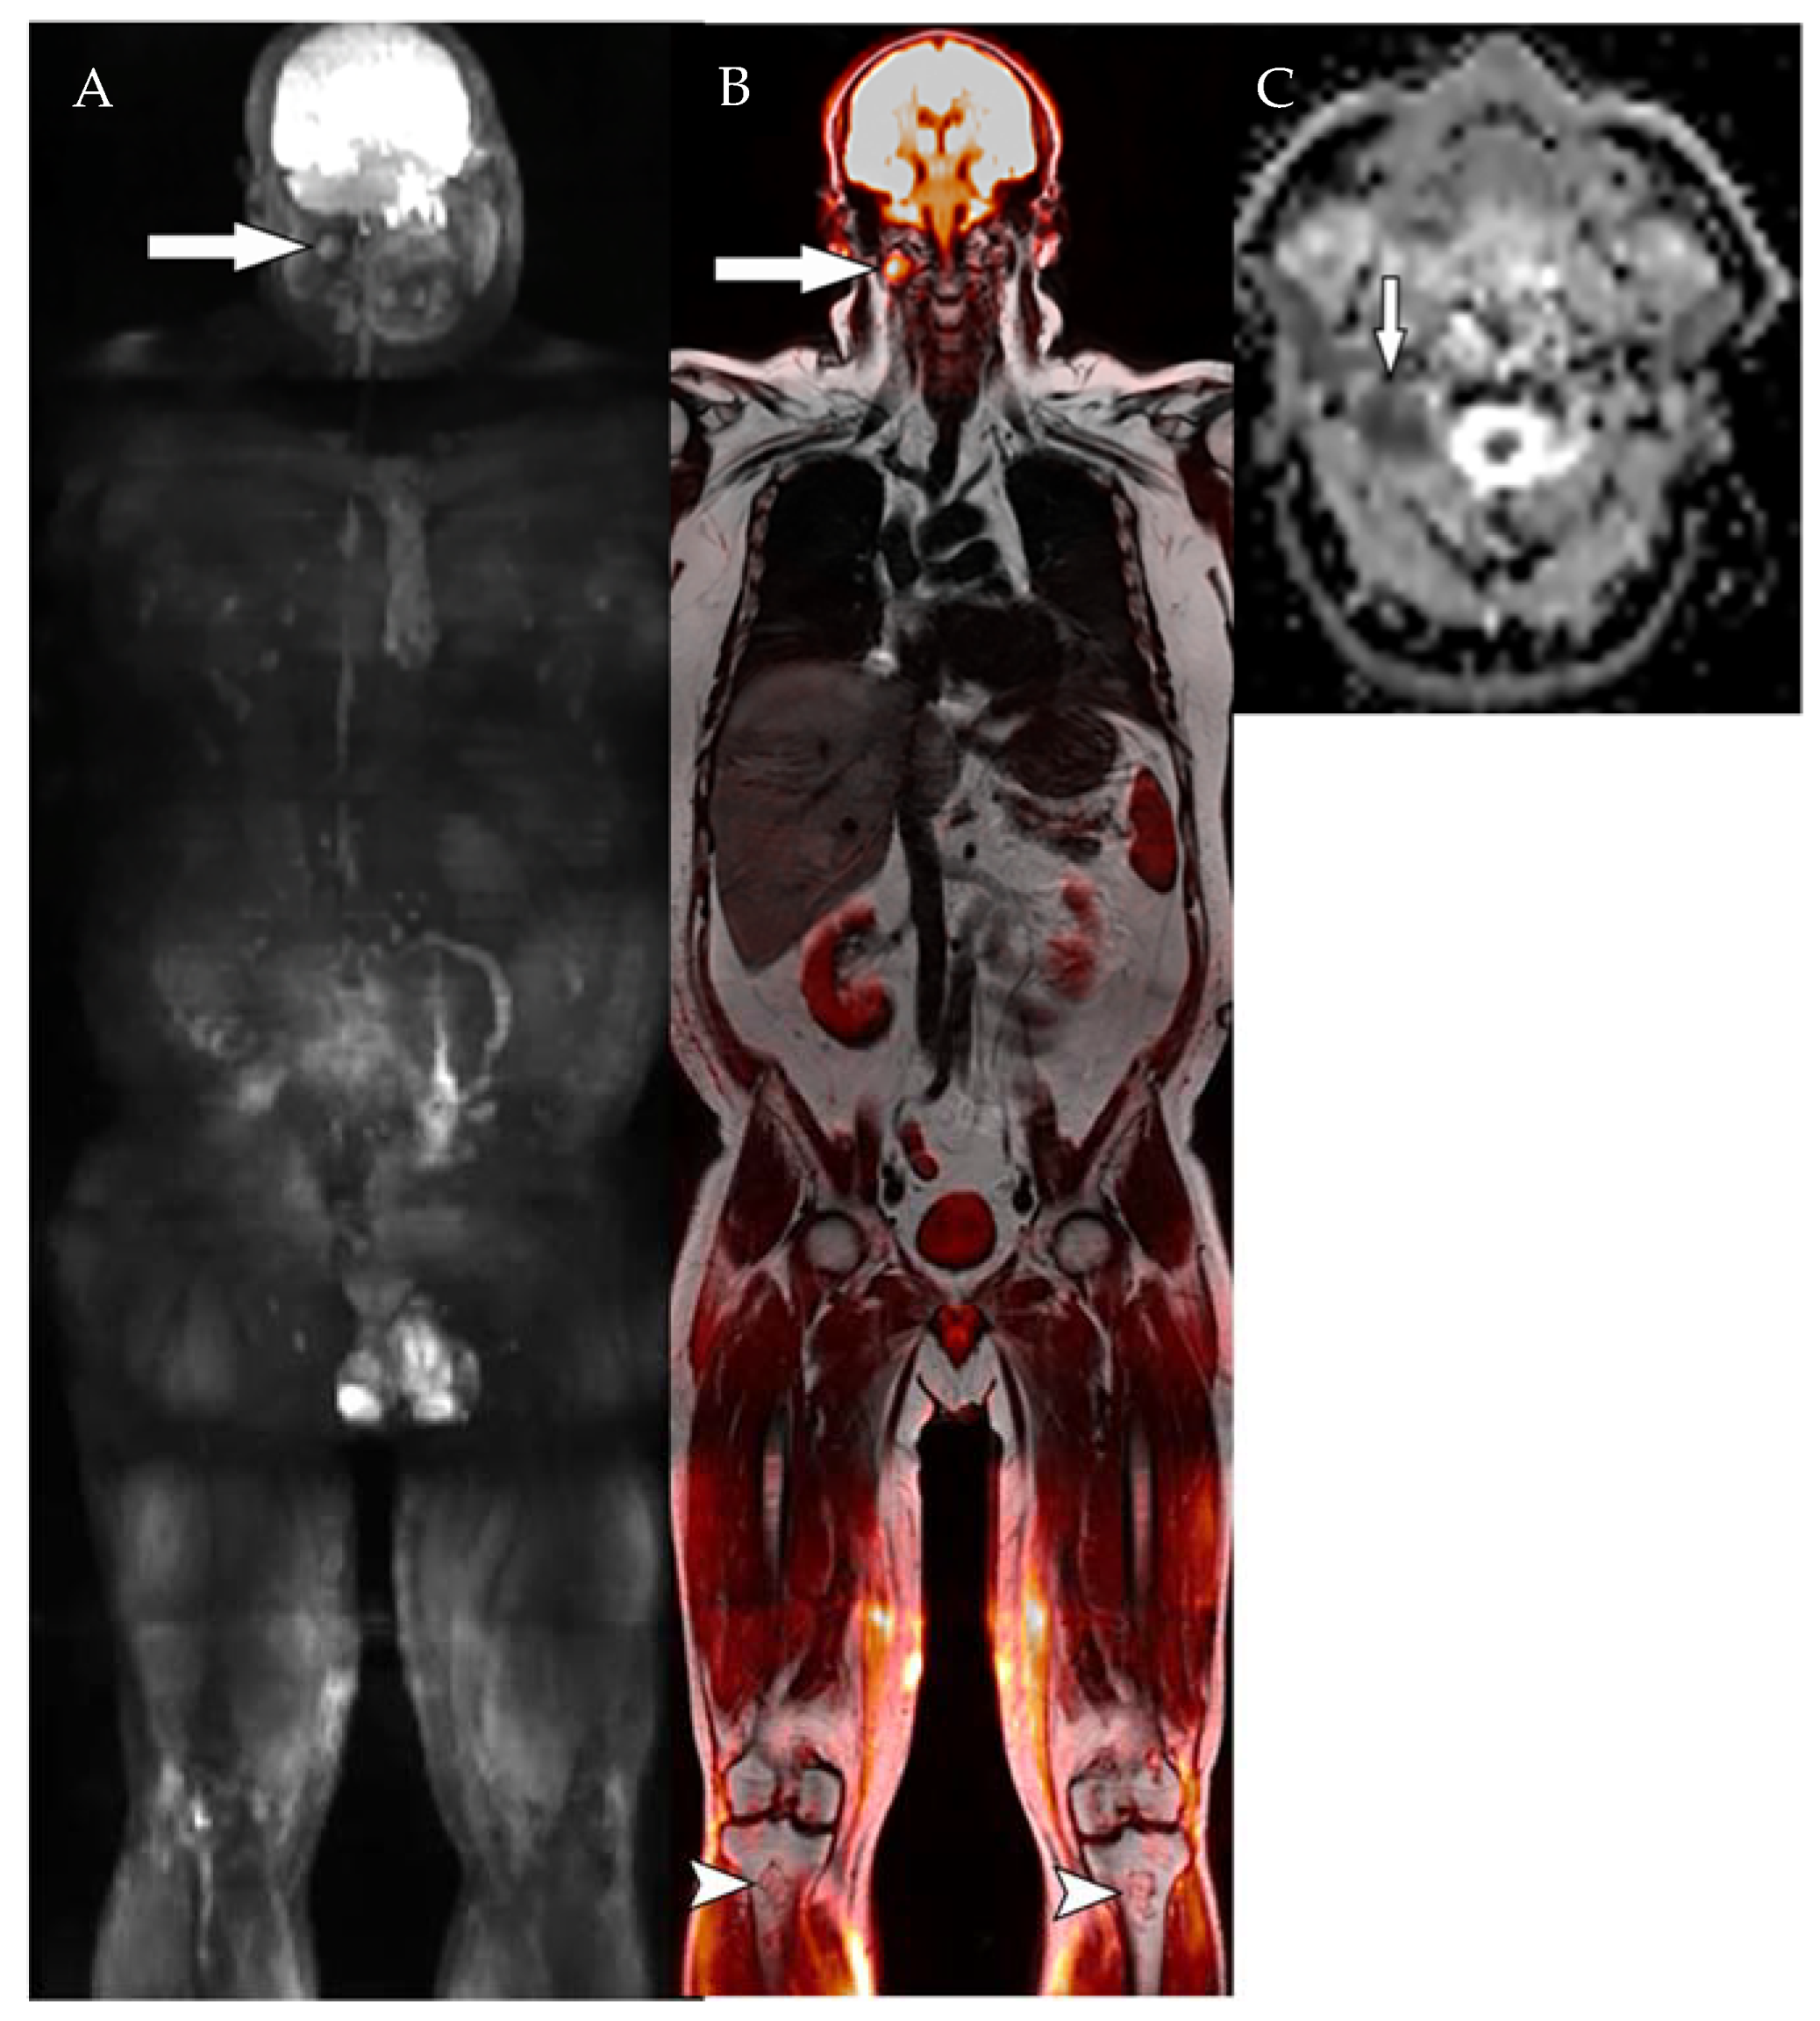

3.3. 18FDG PET/MRI